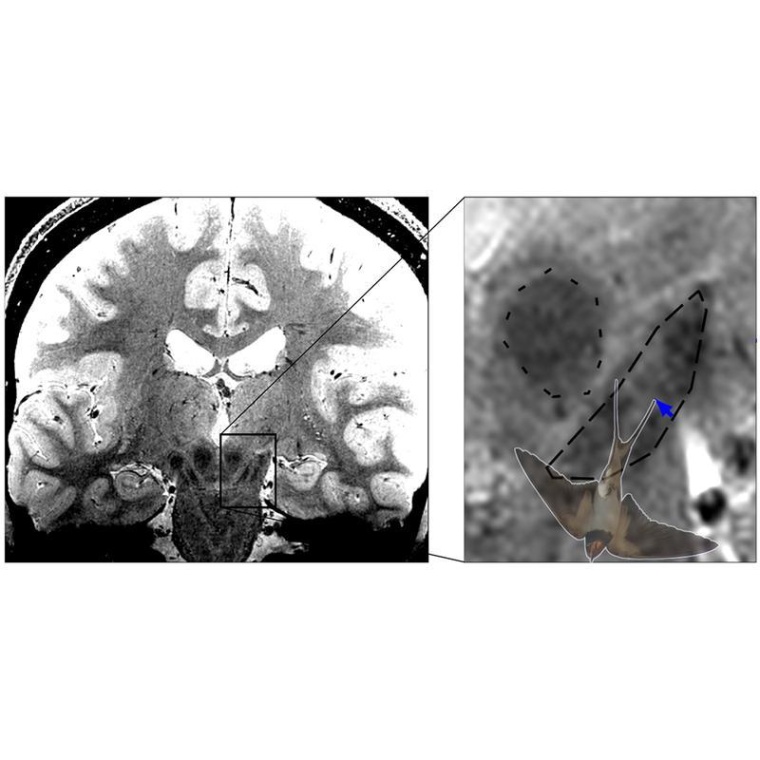

Bei Parkinson sterben dopaminproduzierende Nervenzellen in der Substantia Nigra im Mittelhirn ab, was bei den Betroffenen zu Bewegungsstörungen wie Verlangsamungen, steifen Muskeln und Zittern führt. Besonders stark und früh sind die Nervenzellen im Nigrosom 1 innerhalb der Substantia Nigra betroffen. Mit hochaufgelöster MRT-Bildgebung ist die Abbildung des Schwalbenschwanzzeichens möglich, welches sich im hinteren Drittel der Substantia nigra befindet und nach gängiger Lehrmeinung Nigrosom 1 entspricht. Bei gesunden Menschen erkennt man im MRT-Bild eine signalreiche längliche Struktur, die vorne und an den Seiten von signalarmen Arealen umgeben ist. Diese besondere Form erinnert an einen Schwalbenschwanz, daher spricht man auch vom Schwalbenschwanzzeichen (engl. Swallow tail sign). Nach der gängigen Interpretation des Zeichens führt das Absterben der Neuronen im Nigrosom 1 bei Parkinson-Betroffenen dazu, dass das Schwalbenschwanzzeichen schließlich nicht mehr erkennbar ist. Ist das der Fall, liegt mit hoher Wahrscheinlichkeit eine Parkinson-Erkrankung vor.

Malte Brammerloh und seine Kollegen haben nun mikroskopische 3D-Untersuchungen von menschlichen Gehirnen nach dem Tod mit MRT-Technik kombiniert, um zu zeigen, dass Nigrosom 1 und das radiologische Schwalbenschwanz-Zeichen sich nur teilweise überlappen und in der Tat sehr unterschiedlich sind. Die Wissenschaftler plädieren daher dafür, das Schwalbenschwanz-Zeichen nicht mit der Region Nigrosom 1 gleichzusetzen. Dies erlaubt eine Neuinterpretation des diagnostischen Schwalbenschwanz-Zeichens und eröffnet gleichzeitig neue Wege zur spezifischen Nigrosombildgebung. Brammerloh: „Wir glauben, dass man mit diesem neuen Wissen besser versteht, wie Anatomie und MRT-Kontraste zusammenhängen und wie neue MRT-Marker für die frühe Diagnose von Parkinson entwickelt werden können.“